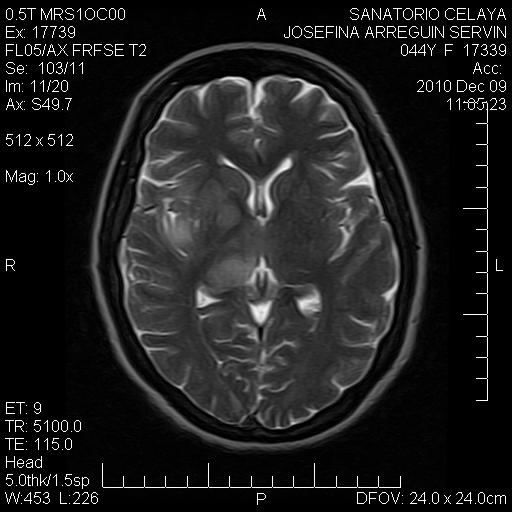

Las imágenes más representativas están aquí,

Se hace notar que la paciente no tiene ni síntomas ni signos de craneo-hipertensivo.